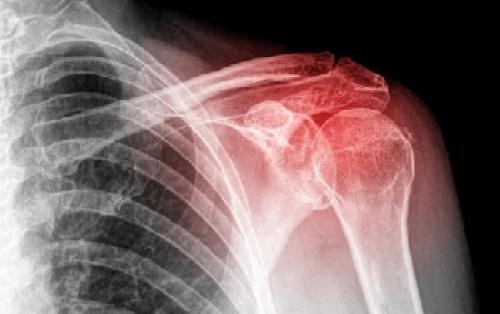

Для точной диагностики артрита плечевого сустава используют методы рентгенографии и компьютерной томографии.

Артроз плечевого сустава

Прогрессирование болезни сопровождается образованием на суставе краевых разрастаний – остеофитов, из-за которых движения становятся болезненными с неприятным хрустящим звуком.

Являются самой распространенной причиной хруста плечевого сустава воспалительной этиологии. Характеризуются ощутимым ограничением движений, острой болью и быстрым прогрессированием течения.

Артриты, как причина хруста в плечевом суставе

В плечевом суставе могут развиться следующие виды артрита:

Является следствием возрастных дегенеративных изменений в тканях после 50 лет. В итоге, истирание хряща ведет к вовлечению поверхности сустава в процессы трения.

Системное заболевание имеет инфекционную природу и поражает синовиальную оболочку сустава. Первые симптомы могут проявиться после физической нагрузки, стресса, переохлаждения.

Развивается вследствие перенесенной травмы – трещины или смещения плечевого сустава, разрыва мышц.

Все эти виды артрита объединены общей симптоматикой – явный щелкающий звук при вращении плеча, ощущения дробленого сустава, постепенно усугубляющаяся боль, затрудненность движений руками.